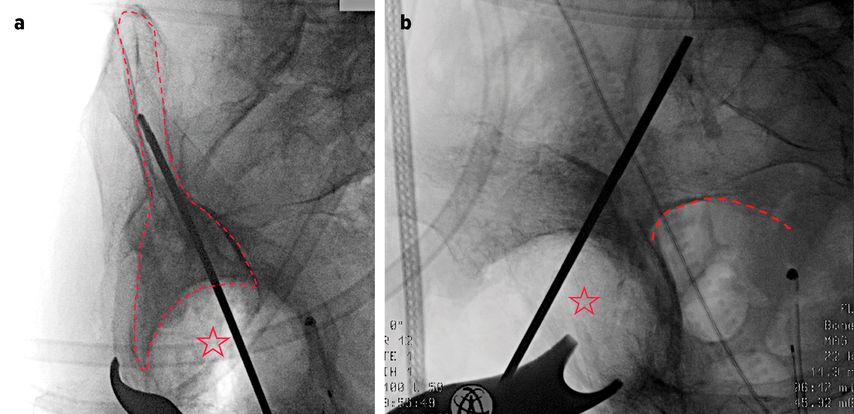

Die PRS-Pfanne zeichnet sich durch ihre massive Bauweise, multiple Schraubenoptionen und die Möglichkeit einer zentralen Ileumschraube aus. Nach Einbringen der Pfanne wird diese korrekt ausgerichtet (Inklination ca. 40–45°, Anteversion ca. 15–20°). Der entscheidende Schritt ist die Platzierung der zentralen Ileumschraube. Dafür wird unter Bildwandlerkontrolle ein Bohrdraht in den supraazetabulären Korridor gesetzt (Abb. 3a u. 3b) und mit dem 6-mm-Bohrer überbohrt. Anschließend wird die Schraube durch das entsprechende Positionsloch der Pfanne in den supraazetabulären Anteil des Iliums eingebracht. Dabei ist auf eine ausreichende Schraubenlänge zu achten, um eine stabile Verankerung zu erzielen. Die zentrale Schraube übernimmt eine lasttragende Funktion und wirkt wie eine intrapelvine Abstützung. Zusätzlich wird die Pfanne mit Schrauben im Sitzbein und/oder dem Schambeinast fixiert (Abb. 4). Die PRS-Pfanne erlaubt hierbei eine flexible Schraubenplatzierung, was insbesondere bei komplexen Frakturmorphologien von Vorteil ist.

Abb. 3a und 3b: a) Positionskontrolle des Führungsdrahtes im supraazetabulären Korridor (gestrichelte Linie) in der Obturator-Aufnahme (Stern: Acetabulum); b) Positionskontrolle des Führungsdrahtes in der Ala-Aufnahme (gestrichelte Linie: Incisura ischiadica major; Stern: Acetabulum)